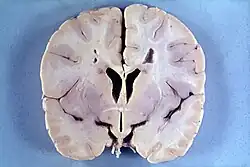

Die Alexander-Krankheit ist primär eine Erkrankung der Astrozyten, Stützzellen des Gehirns (Glia), deren Intermediärfilament GFAP fehlerhaft gebildet wird. Zusammengelagert mit anderen Proteinen bilden sich astrozytäre Einschlüsse, die als Rosenthal-Fasern bekannt sind. Feingeweblich sind Rosenthal-Fasern bei der Erkrankung im gesamten Zentralnervensystem (Gehirn und Rückenmark) nachweisbar, finden sich jedoch bevorzugt periventrikulär und in der Umgebung von Blutgefäßen. Elektronenmikroskopisch zeigt sich eine enge Verbindung der Rosenthal-Fasern mit Intermediärfilamenten.

Darüber hinaus findet sich bei Kindern eine mangelhafte Myelinisierung und bei älteren Patienten eine Entmarkung. Dabei sind sowohl sensorische als auch motorische Nervenfasern betroffen. Die Myelinisierungsstörung wird insbesondere bei kleinen Kindern häufig von einer Makrozephalie und manchmal von einem Hydrozephalus begleitet.

Das Verteilungsmuster der entmyelinisierten Areale stimmt nicht mit dem der Rosenthal-Fasern überein; Myelinisierungsstörung und Faserbildung scheinen also voneinander unabhängige Manifestationen der Krankheit zu sein. Es wird angenommen, dass Veränderungen der Astrozyten sekundär zu einer Myelinisierungsstörung führen.